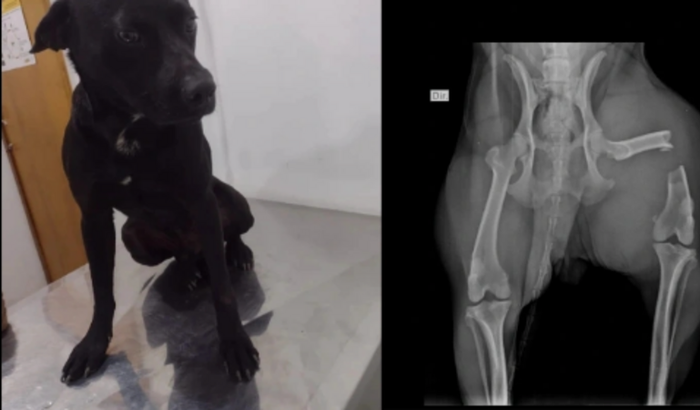

Estamos fazendo essa vakinha para ajudar o negão.Negão é um cão comunitário, que vive em Sardual, petrópolis e esses dias ele foi covardemente atropelado e a pessoa o deixou sem auxílio nenhum. Resolvemos resgata-lo, mas o osso da pata sofreu uma grande lesão, por isso precisará passar por uma cirurgia ortopédica, internação, medicamentos e repouso. Não temos como arcar com todas as despesas, por isso precisamos da sua ajuda.Lembrando que qualquer valor é bem vindo... O pouco p o negão é muito!